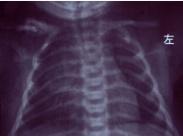

新生兒鎖骨骨折

鎖骨骨折是產傷性骨折中最常見的一種,與分娩方式、胎兒娩出方式位和出生體重有關。難產、胎兒轉位幅度大、巨大兒發生率高。

新生兒產傷是指分娩過程中因機械因素對胎兒或新生兒造成的損傷。近年來由于加強了產前檢查及產科技術提高,產傷發生率已明顯下降,但仍是引起新生兒死亡及遠期致殘原因之一,尤其是在基層單位。鎖骨骨折是產傷性骨折中最常見的一種,與分娩方式、胎兒娩出方位及出生體重有關。